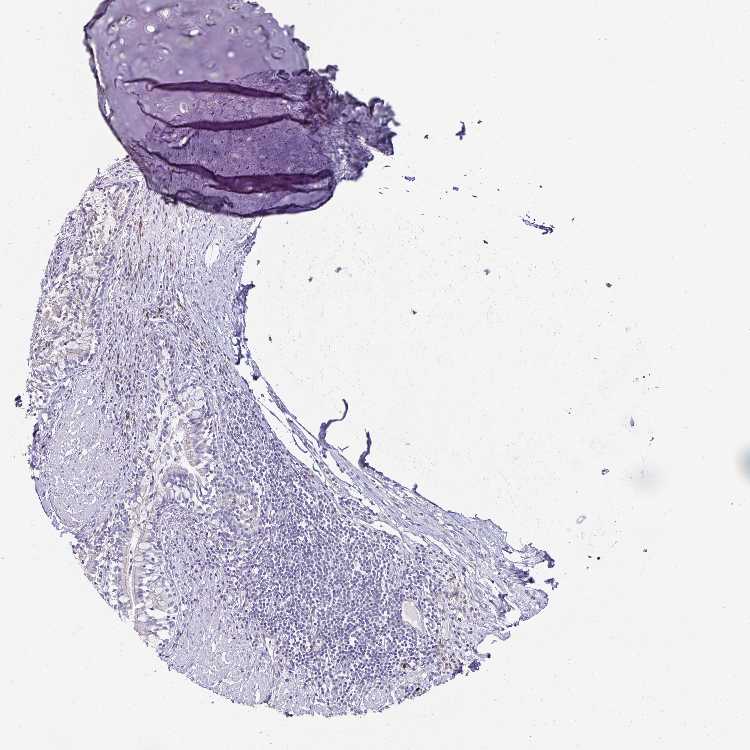

SOFT TISSUE 1 - Antibody stainingi

Antibody staining in the annotated cell types in the current human tissue is reported as not detected, low, medium, or high, based on conventional immunohistochemistry profiling in selected tissues. This score is based on the combination of the staining intensity and fraction of stained cells.

Each image is clickable and will lead to virtual microscopy that enables deeper exploration of all samples and also displays staining intensity scores, fraction scores and subcellular localization as well as patient and tissue information for each sample.

Antibody HPA026744Antibody HPA043297

Chondrocytes -Not detected

Fibroblasts Not detectedLow

Peripheral nerve Not detected-